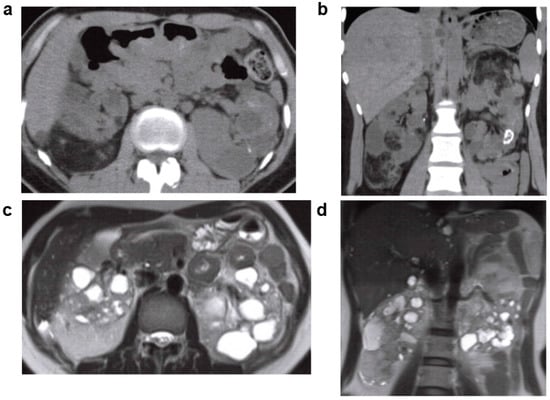

2.2. Acquired Cystic Kidney Disease (ACKD)

- Choyke, P.L. Acquired cystic kidney disease. Eur. Radiol. 2000, 10, 1716–1721. [Google Scholar] [CrossRef]

- Grantham, J.J. Acquired cystic kidney disease. Kidney Int. 1991, 40, 143–152. [Google Scholar] [CrossRef]

- Rahbari-Oskoui, F.; Mittal, A.; Mittal, P.; Chapman, A. Renal relevant radiology: Radiologic imaging in autosomal dominant polycystic kidney disease. Clin. J. Am. Soc. Nephrol. 2014, 9, 406–415. [Google Scholar] [CrossRef] [PubMed]

- Ishikawa, I.; Morita, K.; Hayama, S.; Nakazawa, T.; Araki, I.; Higashi, K.; Miyazawa, K.; Suzuki, K.; Nojima, T. Imaging of acquired cystic disease-associated renal cell carcinoma by contrast-enhanced ultrasonography with perflubutane microbubbles and positron emission tomography-computed tomography. Clin. Exp. Nephrol. 2011, 15, 136–140. [Google Scholar] [CrossRef] [PubMed]

- Kitajima, K.; Yamamoto, S.; Kawanaka, Y.; Katsuura, T.; Fujita, M.; Nakanishi, Y.; Yamada, Y.; Hashimoto, T.; Suzuki, T.; Go, S.; et al. Imaging of renal cell carcinoma in patients with acquired cystic disease of the kidney: Comparison (11)C-choline and FDG PET/CT with dynamic contrast-enhanced CT. Jpn. J. Radiol. 2019, 37, 165–177. [Google Scholar] [CrossRef]

| ACKD | Common | In long-term dialysis patients, the renal parenchyma in both kidneys may show atrophy and proliferation of microcysts. Asymptomatic, but screening for hemorrhage and renal cancer development is necessary. | ||